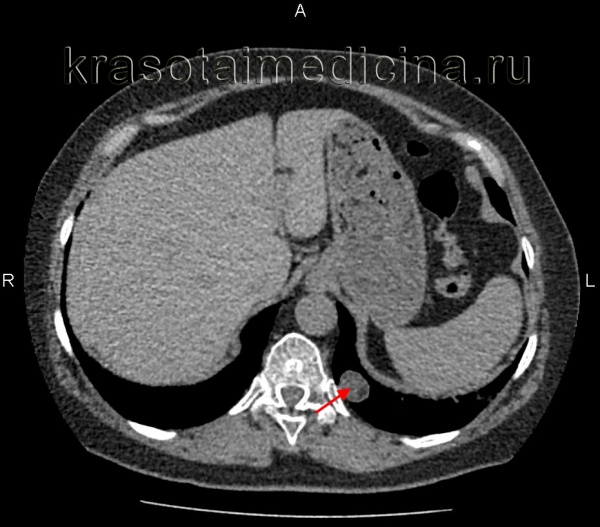

(Слева) МРТ, Т1 -ВИ, сагиттальный срез: у женщины 36 лет, обследованной по поводу судорожного синдрома, визуализируется супраселлярное объемное образование с четкими контурами, расположенное в пределах III желудочка.

(Справа) Тонкосрезовое корональное IR изображение: определяется объемное образование, расположенное в гипоталамусе. Это образование изоинтенсивно по отношению к серому веществу.

(Слева) МРТ, Т2-ВИ, корональный срез: у этой же пациентки объемное образование остается изоинтенсивным по отношению к серому веществу и на данной последовательности; оно приподнимает III желудочек, но не вызывает его обструкцию.

(Справа) МРТ, FLAIR, корональный срез: у этой же пациентки визуализируется образование, имеющее слегка повышенную интенсивность сигнала по отношению к коре. После введения контрастного вещества объемное образование его не накапливало. Это классическая гамартома гипоталамуса (ГГ) на широком основании.